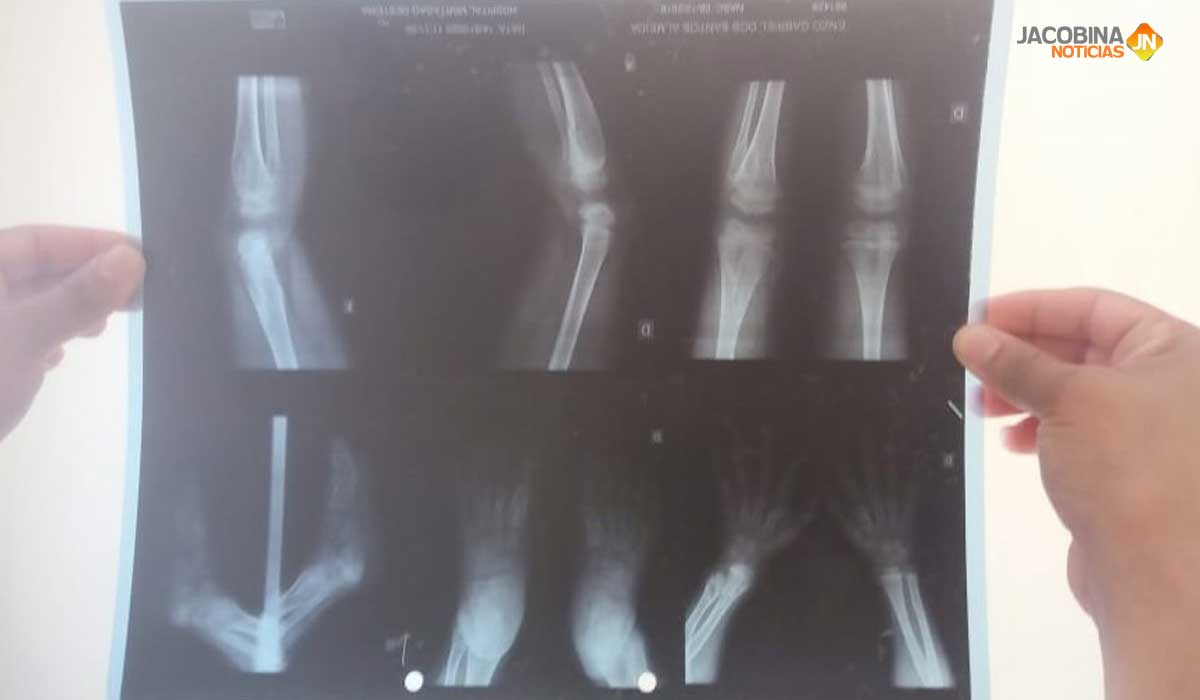

Genevaldo Santana Nascimento, 18 anos, e Fernanda Santos Dutra, 26 anos, deixaram a cidade de Mundo Novo, onde residiam, para morar em Jacobina, no Piemonte da Chapada Diamantina, há alguns meses. O motivo foi a busca por tratamento de saúde para o filho Enzo Gabriel Santos Almeida, de 4 anos, diagnosticado com encondromatose múltipla – doença genética irreversível que causa deformidades ou ressecção de tumores nos ossos.